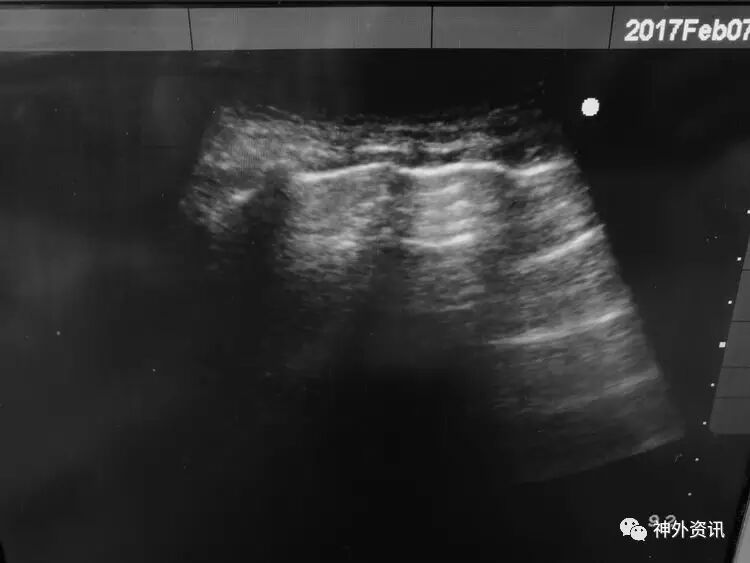

患儿刘**,男,19个月,2017.1.30 2pm不慎摔倒,意识障碍,刺痛不睁眼,不发音,刺痛肢体屈曲,急至当地医院,伤后1小时颅脑CT结果示右额颞顶枕急性硬膜下血肿,中线轻微左移: